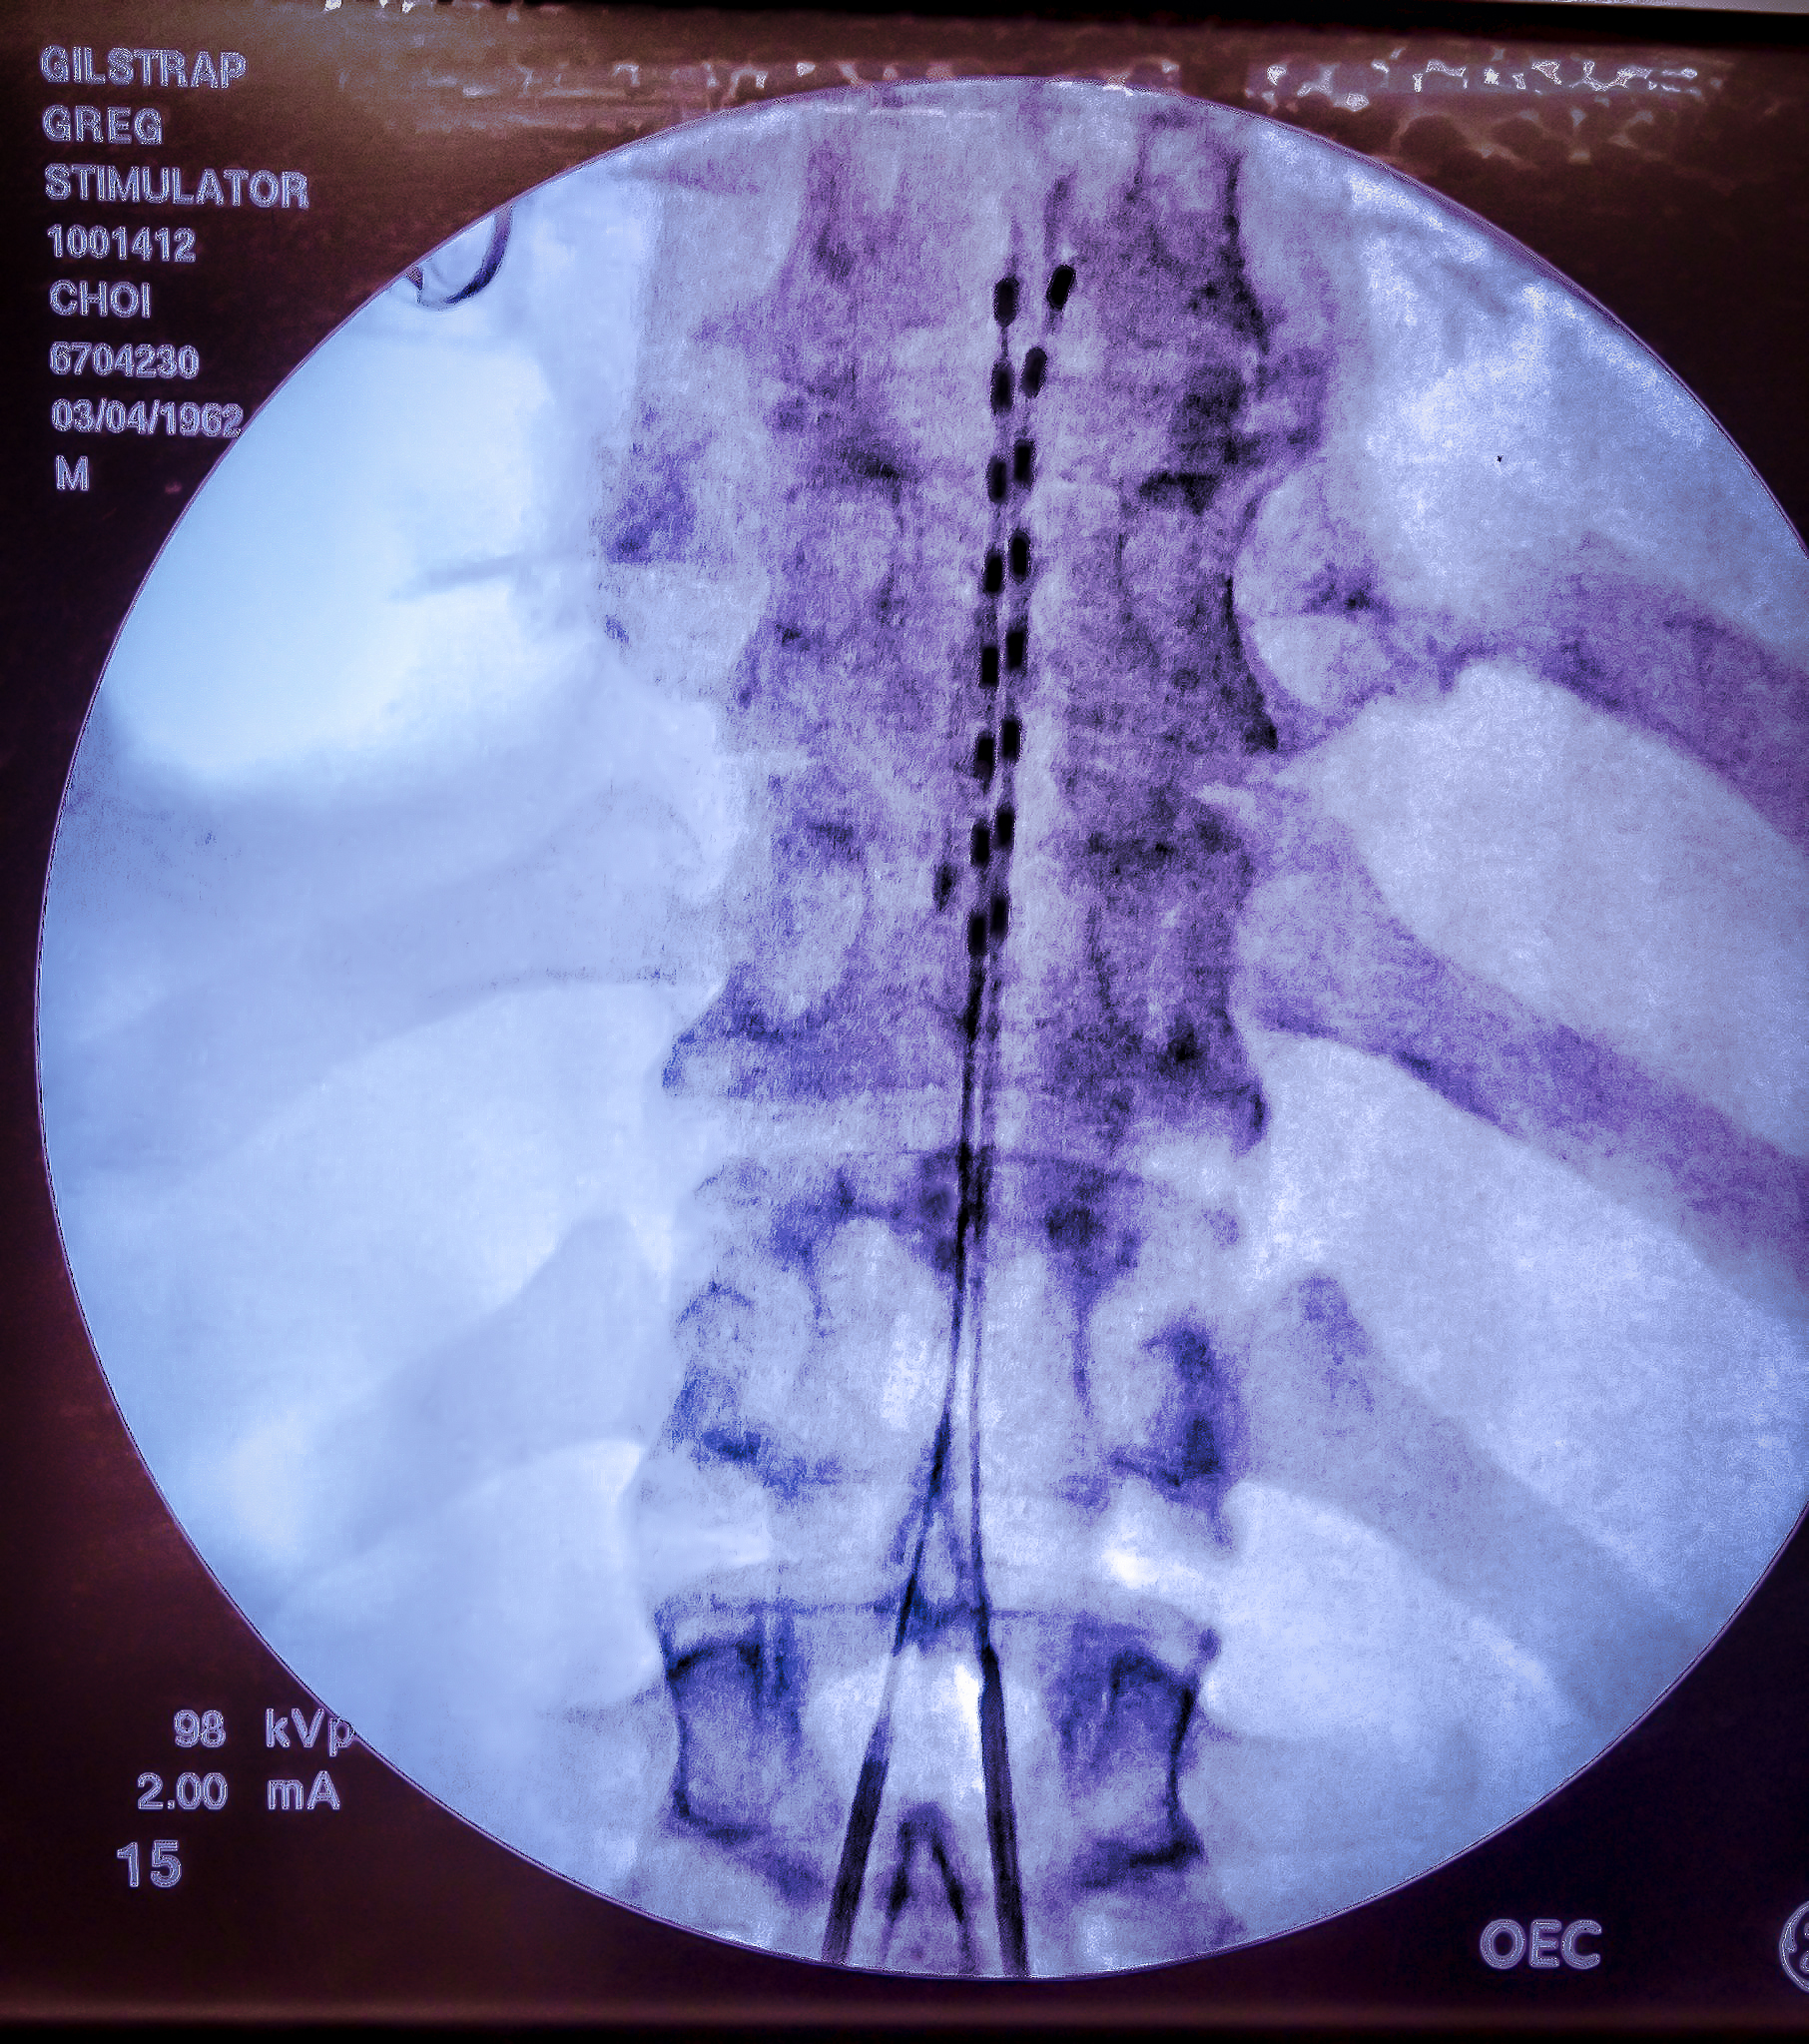

As described on our blog’s About Page, I have a variety of pain-fighting tools at my disposal. They range from two neurostimulators (or generators) that have been implanted in my spine and stretching to multiple ice packs–I typically spend 2-3 hours on ice every day– and prescription medications.